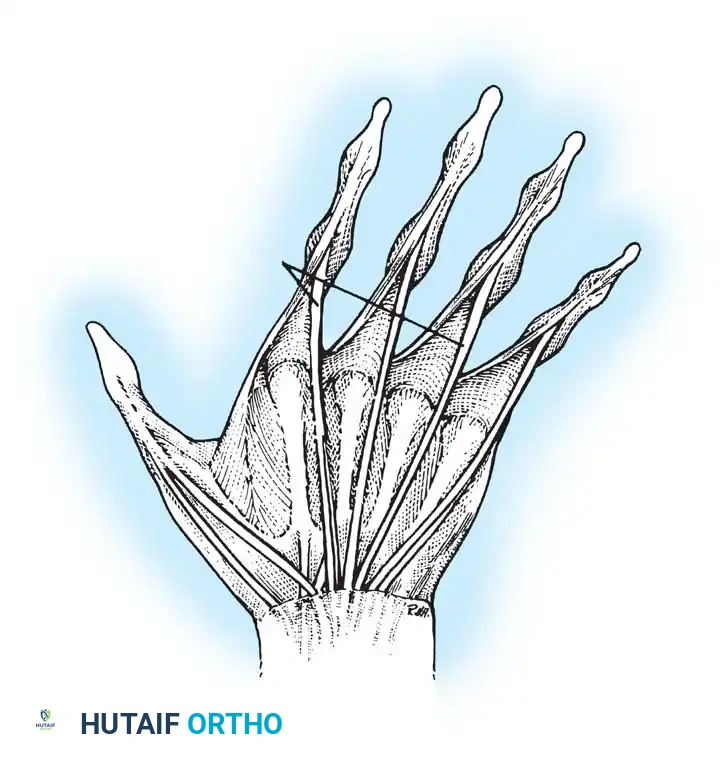

Deformities of the fingers in rheumatoid arthritis (RA) are the culmination of destructive synovitis interacting with the complex biomechanical forces of the hand. These deformities are driven by normal forces applied to joints that have been structurally compromised by the disease process. The extrinsic flexors and extensors, combined with the tightness of the intrinsic muscles, exert deforming forces on attenuated capsuloligamentous structures.

Specific anatomical failures include the displacement of the lateral bands of the extensor hood, rupture of the central slip, or attritional rupture of the long extensor or flexor tendons. Furthermore, abnormal forces act on joints already weakened by erosive pannus. Flexor tenosynovitis frequently produces a mechanical limitation of interphalangeal (IP) joint motion; consequently, the range of active flexion in these joints is significantly less than passive flexion.

INTRINSIC PLUS DEFORMITY

The intrinsic plus deformity is characterized by flexion of the metacarpophalangeal (MCP) joints and extension of the proximal interphalangeal (PIP) joints. It is caused by the tightness, spasm, and eventual ischemic contracture of the intrinsic muscles (lumbricals and interossei) secondary to rheumatoid inflammation.

In hands with a fixed intrinsic plus deformity, the PIP joint cannot be flexed while the MCP joint is fully extended. This deformity frequently develops in combination with volar subluxation of the MCP joints and ulnar deviation of the fingers.

Release of the volar intrinsics, especially the abductor digiti quinti, was previously thought to reduce ulnar drift when performed early. However, it is usually ineffective in isolation because factors other than tight intrinsics (e.g., radial deviation of the wrist, volar plate attenuation) contribute heavily to the deformity.

When indicated, intrinsic tightness may be released in conjunction with MCP synovectomy by mobilization of the lateral bands. If severe degeneration of the MCP joints requires arthroplasty, the resection of the metacarpal head often shortens the skeletal framework sufficiently to relax the intrinsic mechanism without requiring a formal release.